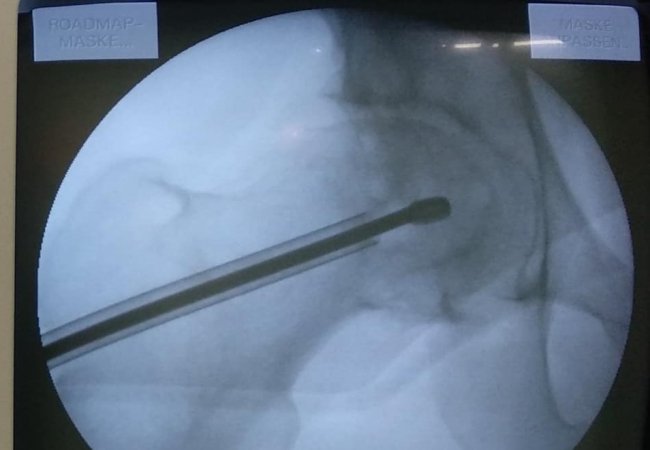

В ході подальшого дослідження в головці правої стегнової кістки виявили кисту розмірами 2*2*2,5 см.

"В ході клінічного розбору було прийняте рішення на користь органозберігаючої операції. Куратор напрямку пухлин та пухлиноподібних захворювань Шевчик Я.В. виконав унікальну операцію: декомпресійну пластику кисти головки стегнової кістки", - йдеться в дописі.

Ця операція полягає у видаленні вмісту кисти, очищенні її стінок та виповнення дефекту кістковим трансплантатом з доступу розміром 3 см.